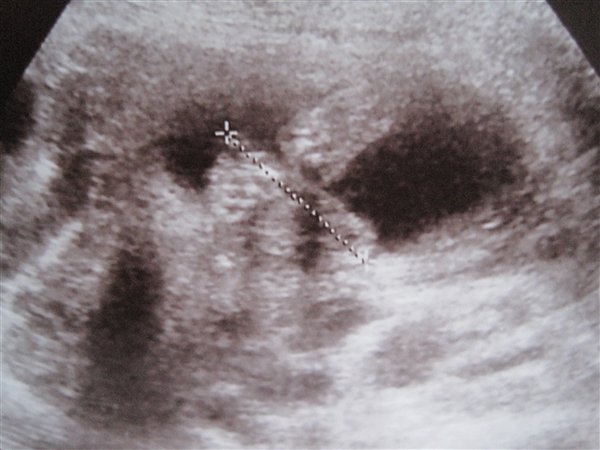

Så er Md-scanningen overstået og det gik rigtig godt.... Fik rigtig meget "ros" Hende der scannede sagde at det så rigtig fin ud og at det var en god stor baby.... Meget stor faktisk, hun sagde der var ik noget at sige til jeg havde tabt mig 6 kg for den lille tog da alt min næring!

Og det er en DRENG